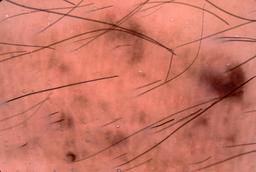

{

"age_approx": 55,

"anatom_site_general": "lower extremity",

"concomitant_biopsy": true,

"dermoscopic_type": "contact non-polarized",

"diagnosis_1": "Malignant",

"diagnosis_2": "Malignant adnexal epithelial proliferations - Follicular",

"diagnosis_3": "Basal cell carcinoma",

"diagnosis_confirm_type": "histopathology",

"image_type": "dermoscopic",

"lesion_id": "IL_9320857",

"melanocytic": false,

"patient_id": "IP_5255747",

"sex": "female"